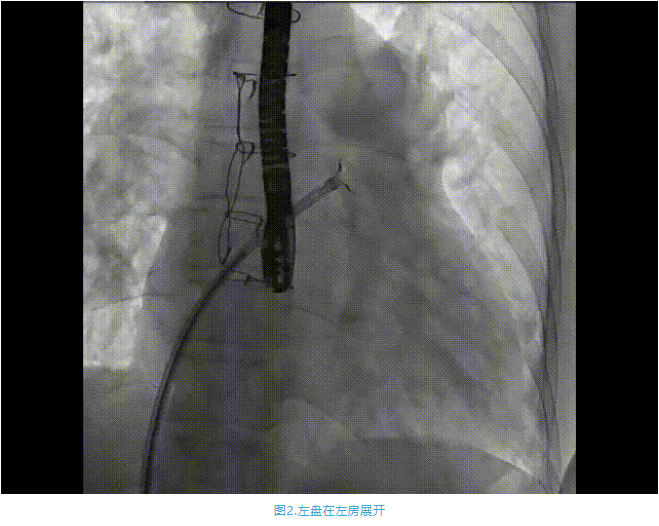

術(shù)中首先在局麻下穿刺股動脈、股靜脈,完成心導(dǎo)管檢查評估后轉(zhuǎn)為全麻,在食道超聲引導(dǎo)下穿刺房間隔,穿刺成功后將加硬導(dǎo)絲送入左上肺靜脈建立軌道,根據(jù)患者病情行球囊預(yù)擴張后植入6mm孔徑房間隔造孔支架,經(jīng)透視及食道超聲評估支架左右盤展開良好,夾持于房間隔兩側(cè),固定穩(wěn)定、位置良好,食道彩超顯示房水平右向左為主分流,分流孔直徑符合預(yù)期大小,心導(dǎo)管檢查評估達到預(yù)期效果,釋放造孔支架。術(shù)后12h患者下床活動,恢復(fù)順利,擬于近日完善術(shù)后評估后出院。